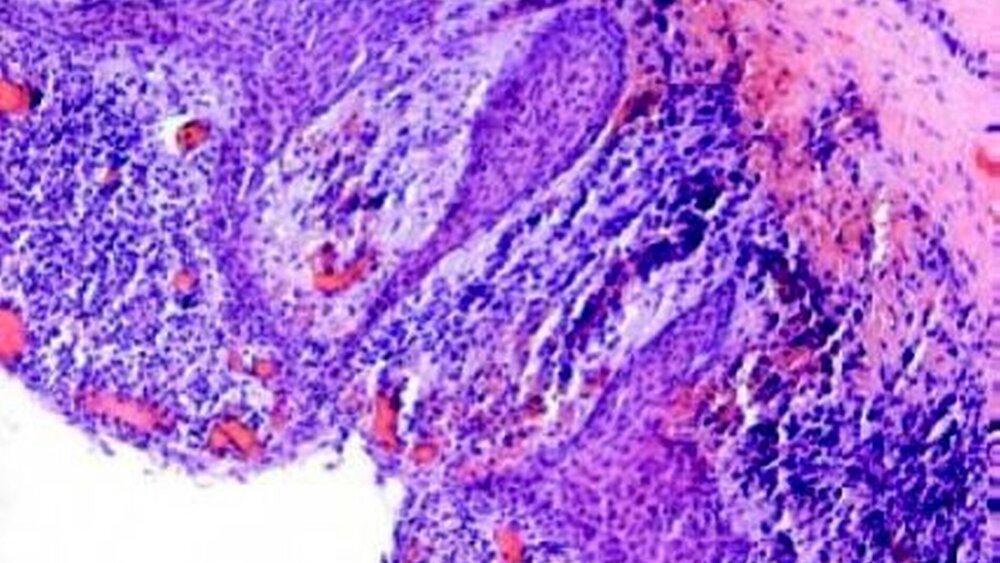

Die histopathologische Begutachtung der Präparate ergab ausgedehnte radikuläre Zysten (Abbildung 5). Bei der radiologischen Kontrolle nach einem halben Jahr zeigten sich die Radioluzenzen deutlich rückläufig, klinisch fanden sich unauffällige Verhältnisse.

Die radikuläre Zyste ist eine in der Regel einkammerige sich auf einer entzündlichen Basis bildende odontogene Zyste, die sich durch Proliferation aus einem apikalen Granulom, seltener einer Parodontitis, durch Einwachsen des Epithels aus Mallassez-Epithelnestern, den Resten der Hertwig-Epithelscheide oder des Saumepithels entwickelt [Regezi 2008]. Die radikuläre Zyste ist mit 50 bis 80 Prozent die häufigste odontogene Zyste. Sie ist im Oberkiefer etwa doppelt so häufig vertreten wie im Unterkiefer [Meningaud et al., 2006; Tortorici et al., 2008]. Pathohistologisch ist ein dreischichtiger Wandaufbau charakteristisch. Die innere epitheliale Schicht besteht aus einem mehrschichtigen Plattenepithel, daran angrenzend findet sich oftmals eine Zone entzündlichen Infiltrats und abschließend kollagenfaserreiches, zellarmes Bindegewebe.